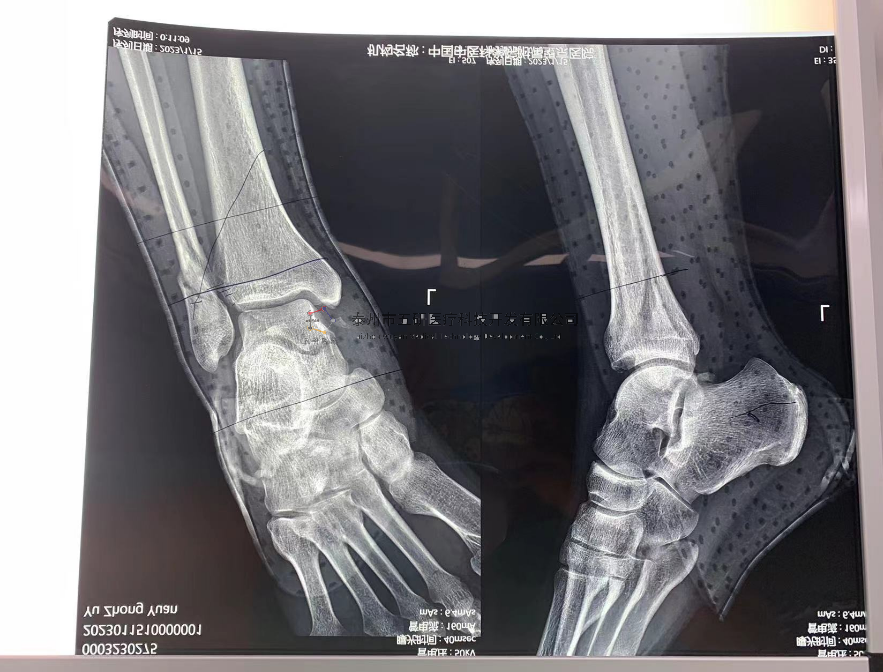

【所屬科室】中國中醫(yī)科學院望京醫(yī)院創(chuàng)一科

【基本資料】患者,男,65歲

【患者情況】脛骨遠端骨折伴腓骨骨折

【影像圖片—術前】

【影像圖片—術后】